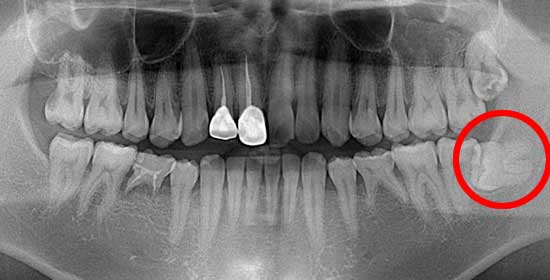

術前後のレントゲン写真

このように横に生えていると、7番目の歯と親知らずの隙間に細菌が溜まり、虫歯になったり、周囲の歯肉が腫れたりする原因となります。

術 前

術 後